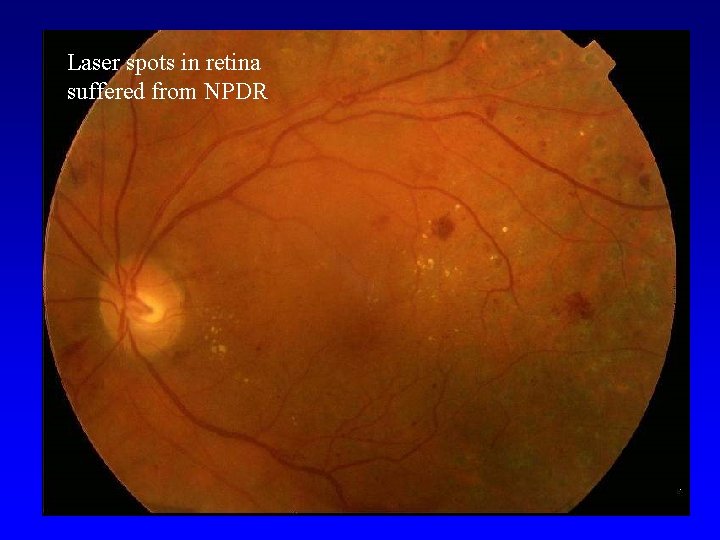

Laser spots in retina suffered from NPDR